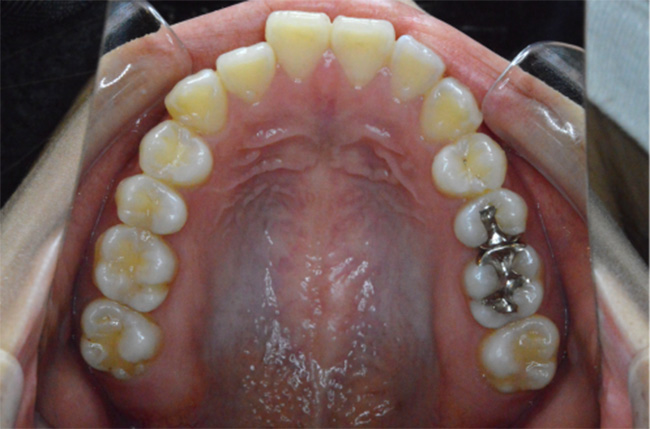

治療開始時